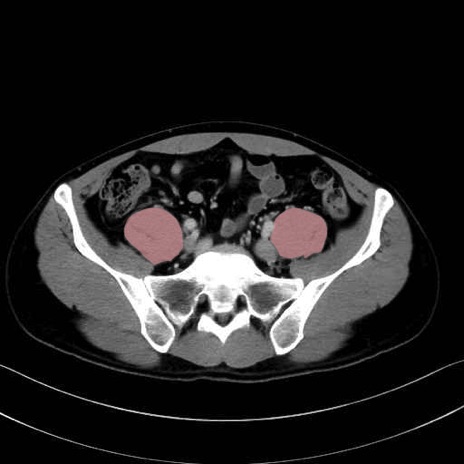

2. 腸腰筋群と骨盤底筋

大腰筋 (Psoas major)

腸骨筋 (Iliacus)